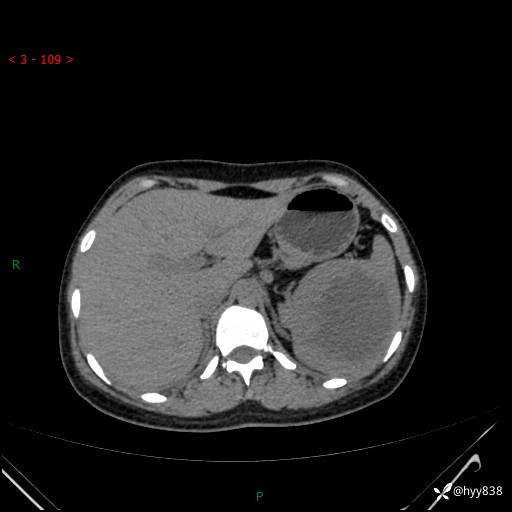

患者性别:男

患者年龄:44岁

主诉:外院超声发现脾脏占位,来我院进一步诊治。

临床诊断:脾脏占位

脾脏CT平扫+增强(动脉期+静脉期)